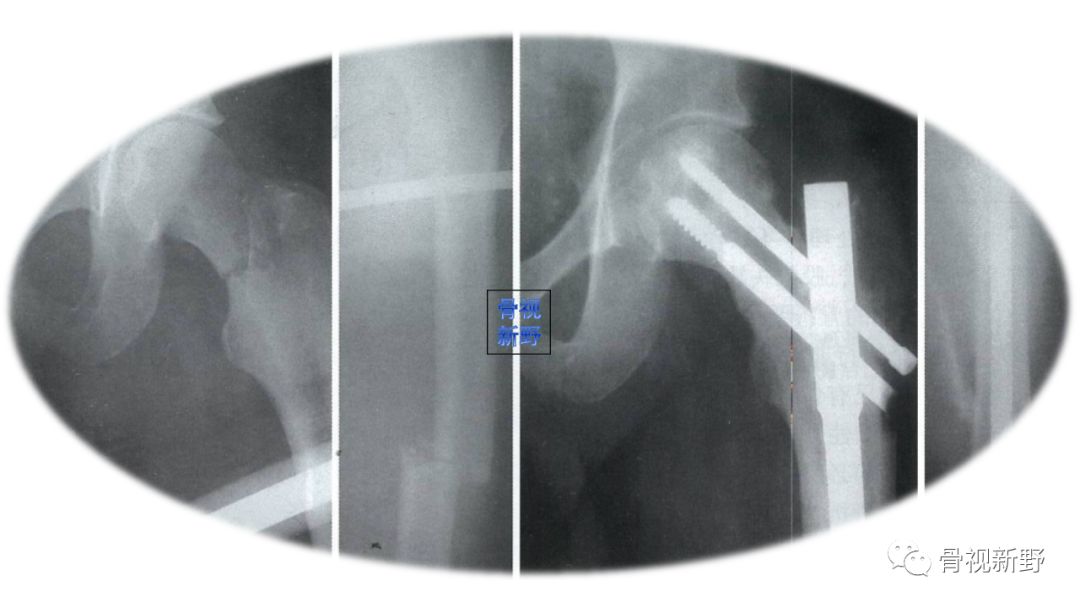

文献报道,Pauwels Ⅲ型股骨颈骨折多由高能量损伤所致,多为青壮年患者。由于垂直剪力较大,易于内翻,固定失败。其骨不连达16-59% ;股骨头坏死率达11-86%[Protzman 1976; Liporace 2008]。

传统的多枚空心钉平行加压固定并不能完全解决稳定性问题,近年来出现了一些新的优化固定理念及其固定方式,有部分与传统固定方式进行了固定强度的比较(如下图示);有的尚未得到大样本、多中心的临床随机对照实验(RCTs), 仅供参考。